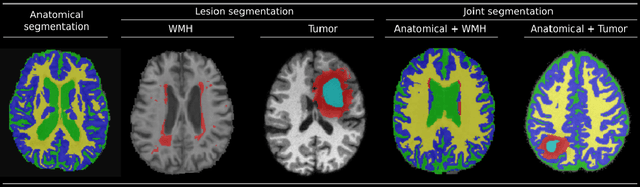

Brain lesion and anatomy segmentation in magnetic resonance images are fundamental tasks in neuroimaging research and clinical practice. Given enough training data, convolutional neuronal networks (CNN) proved to outperform all existent techniques in both tasks independently. However, to date, little work has been done regarding simultaneous learning of brain lesion and anatomy segmentation from disjoint datasets. In this work we focus on training a single CNN model to predict brain tissue and lesion segmentations using heterogeneous datasets labeled independently, according to only one of these tasks (a common scenario when using publicly available datasets). We show that label contradiction issues can arise in this case, and propose a novel adaptive cross entropy (ACE) loss function that makes such training possible. We provide quantitative evaluation in two different scenarios, benchmarking the proposed method in comparison with a multi-network approach. Our experiments suggest that ACE loss enables training of single models when standard cross entropy and Dice loss functions tend to fail. Moreover, we show that it is possible to achieve competitive results when comparing with multiple networks trained for independent tasks.